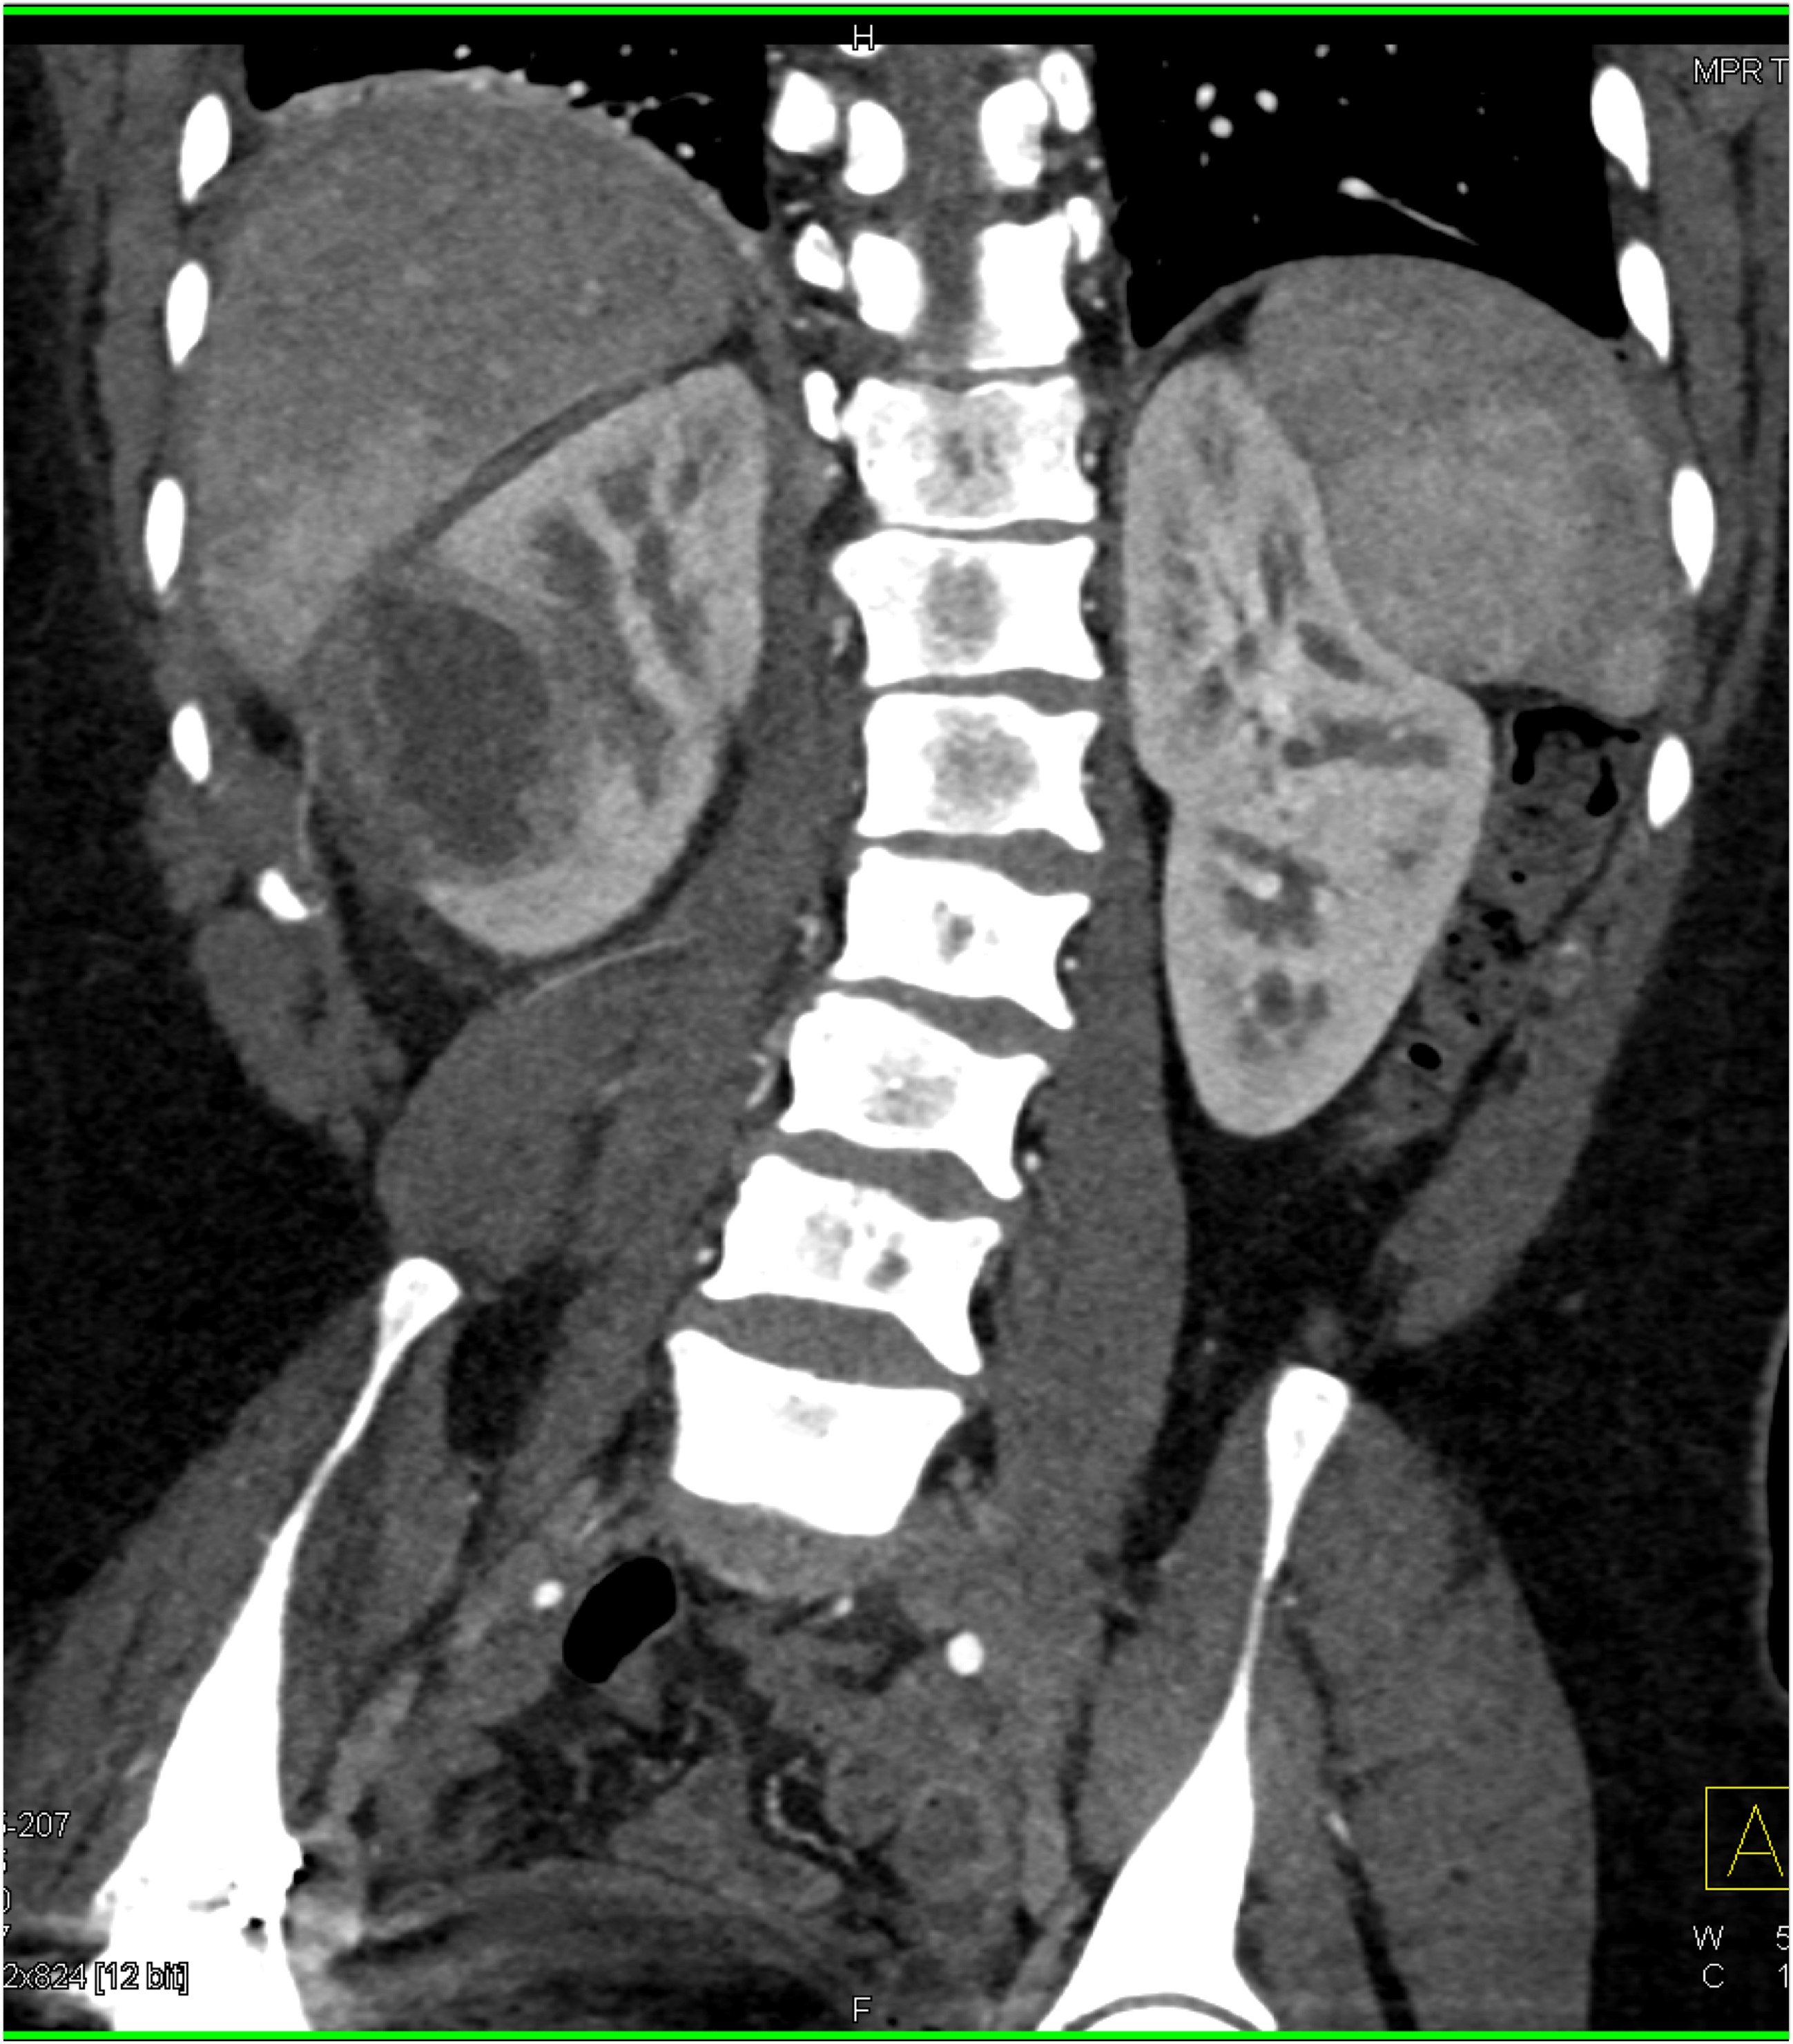

4) In this patient with sickle cell disease the most likely diagnosis is?

lymphoma

renal cell carcinoma

renal abscess

MEST tumor